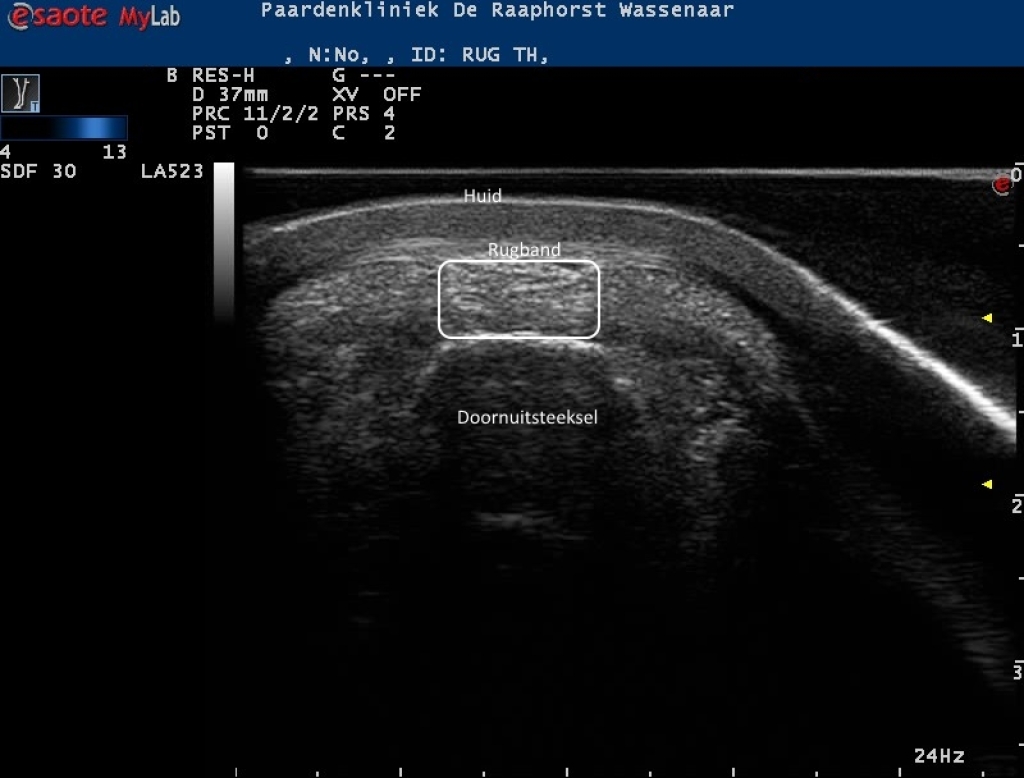

Rechts: Echobeeld van de rugband boven een doornuitsteeksel

Echobeeld van de rugband boven een doornuitsteeksel

Echobeelden van de lengte en dwarsdoorsnede van de rugband

Foto: Echobeelden van de lengte en dwarsdoorsnede van de rugband